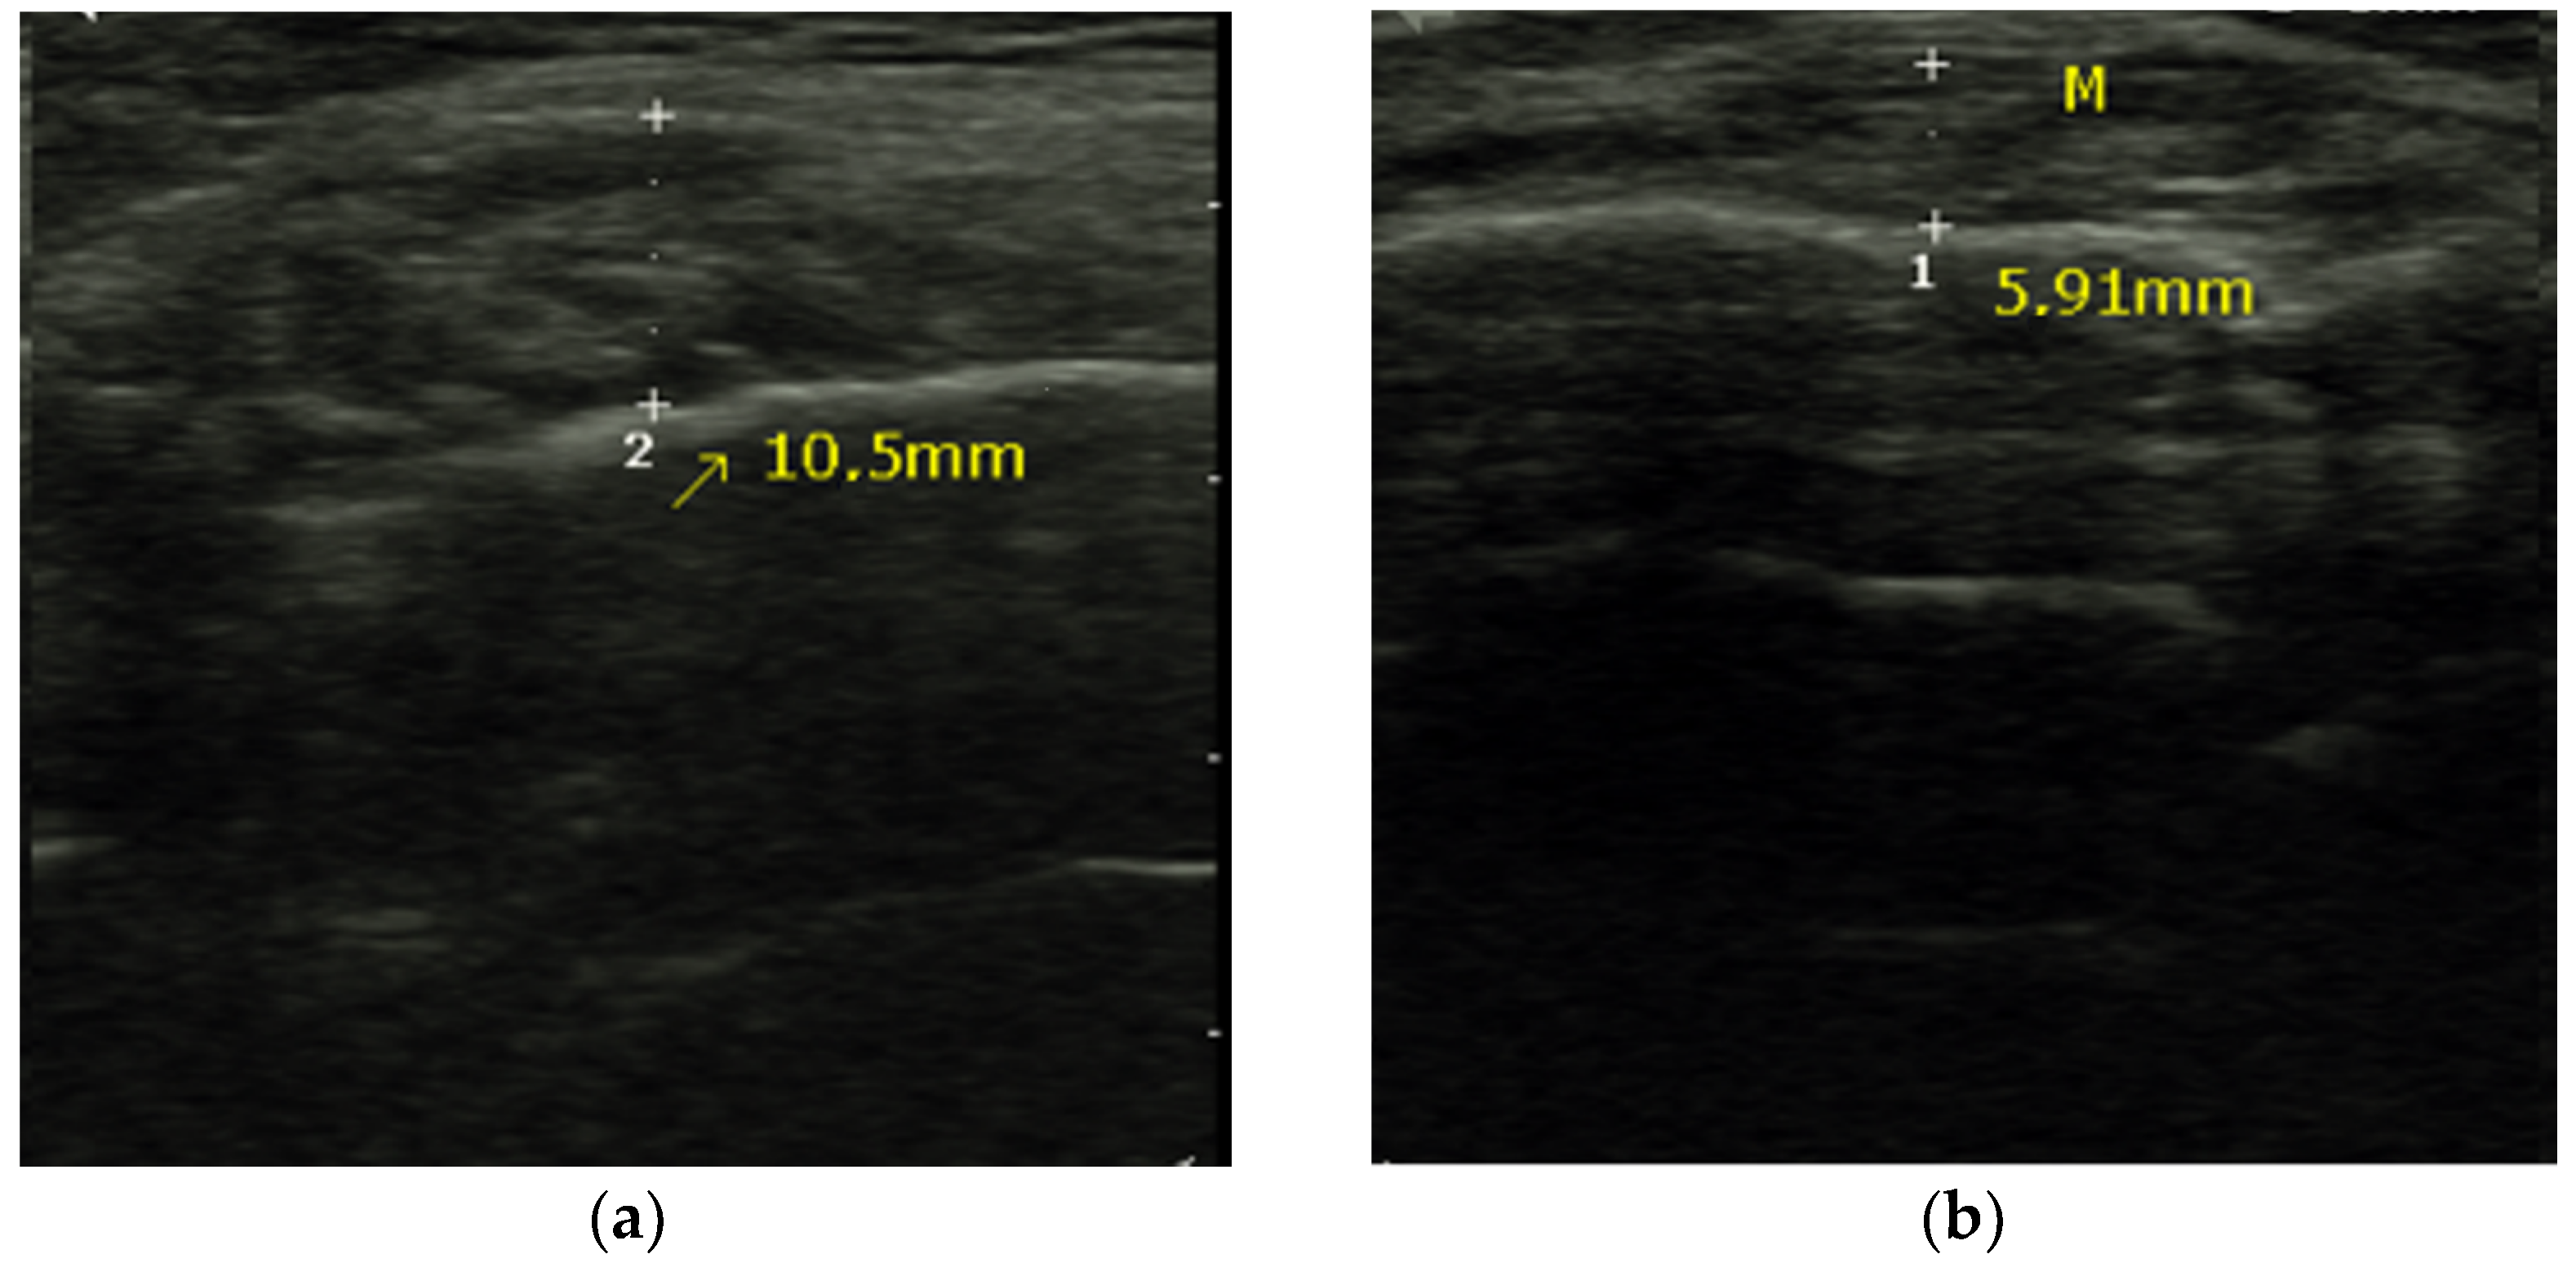

2.4. Masseter Muscle Thickness Measurement